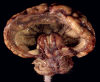

Occipital View: The cerebral hemispheres shows that the

occipital portion is reduced to a thin translucent seam

(white arrow). This is best

illustrated in the image with the specimen submerged under water. The

occipital portion of the parietal and occipital pallium is entirely

converted into a thin membrane. The thalamus and the basal ganglia appear to

have split into the left and right half. There is a single,

dilated ventricle with no septum pellucidum.